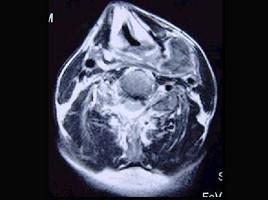

问题 男性,40岁,发现左侧颈部小包块,CT、MRI检查如图所示,请选择最可能的诊断 ( )

选项 A、肿大淋巴结 B、副神经节瘤 C、神经纤维瘤 D、海绵状血管瘤 E、神经鞘瘤

答案 D